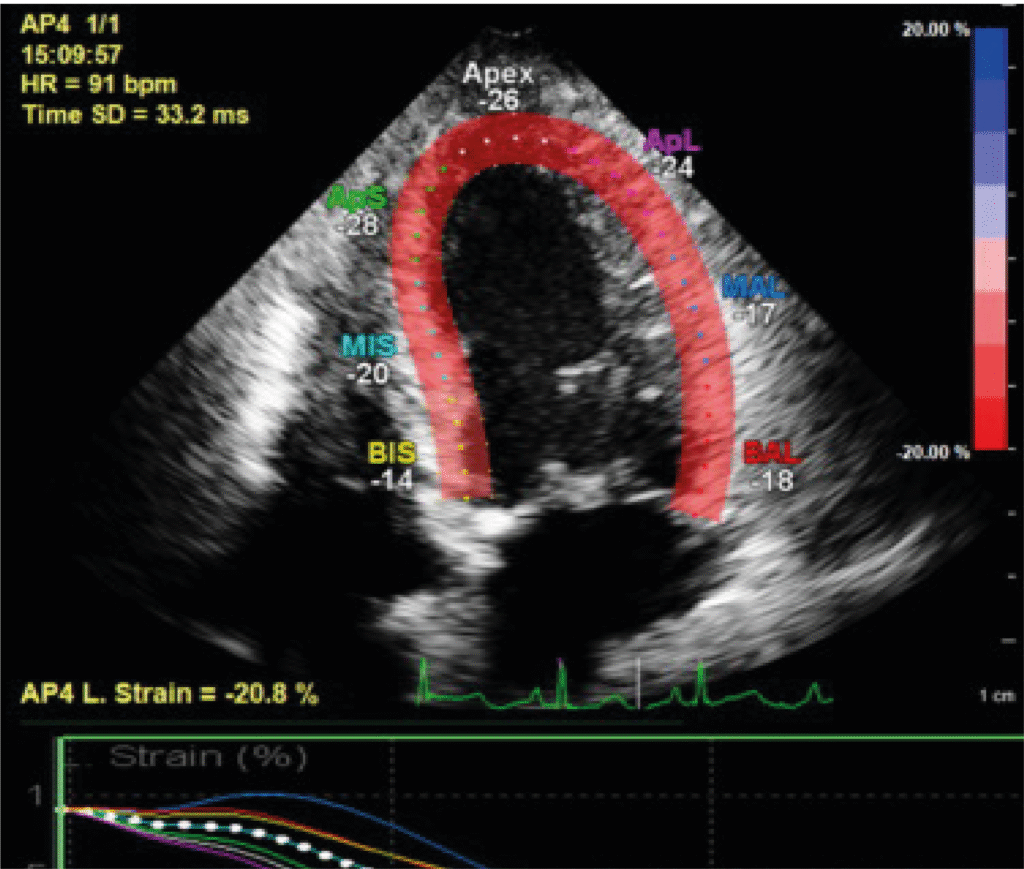

Strain Imaging

Strain imaging, a sophisticated echocardiographic tool, allows for the early detection of subtle myocardial dysfunction, even before conventional imaging shows abnormalities. By measuring deformation of heart muscle fibres, it aids in diagnosing cardiomyopathies, chemotherapy-related heart damage, and early heart failure.